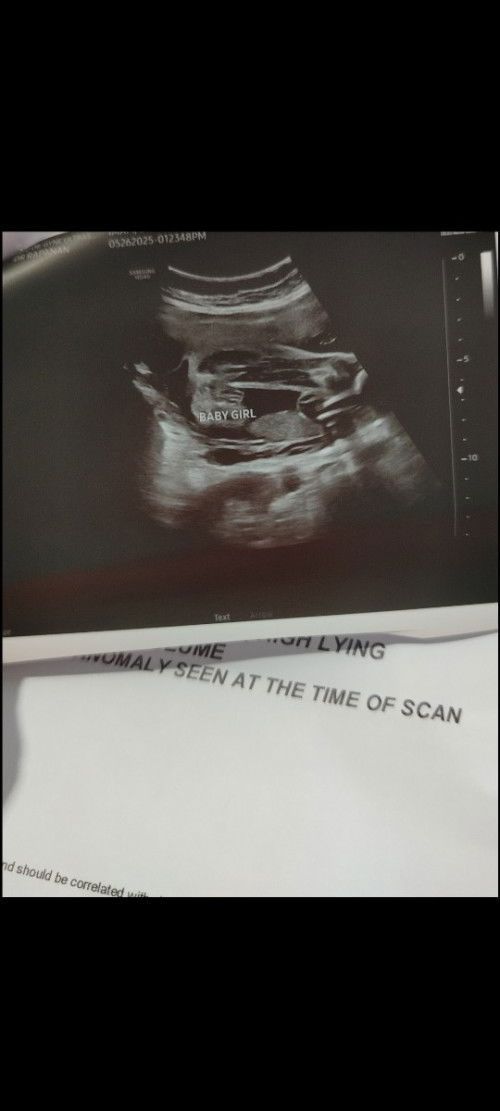

mga mommy, sure na kaya ito na baby girl.? subrang excited na kasi ako...may 2boy na kasi ako

CAS ultrasound #pregnancy #askmommies #2dtrimester